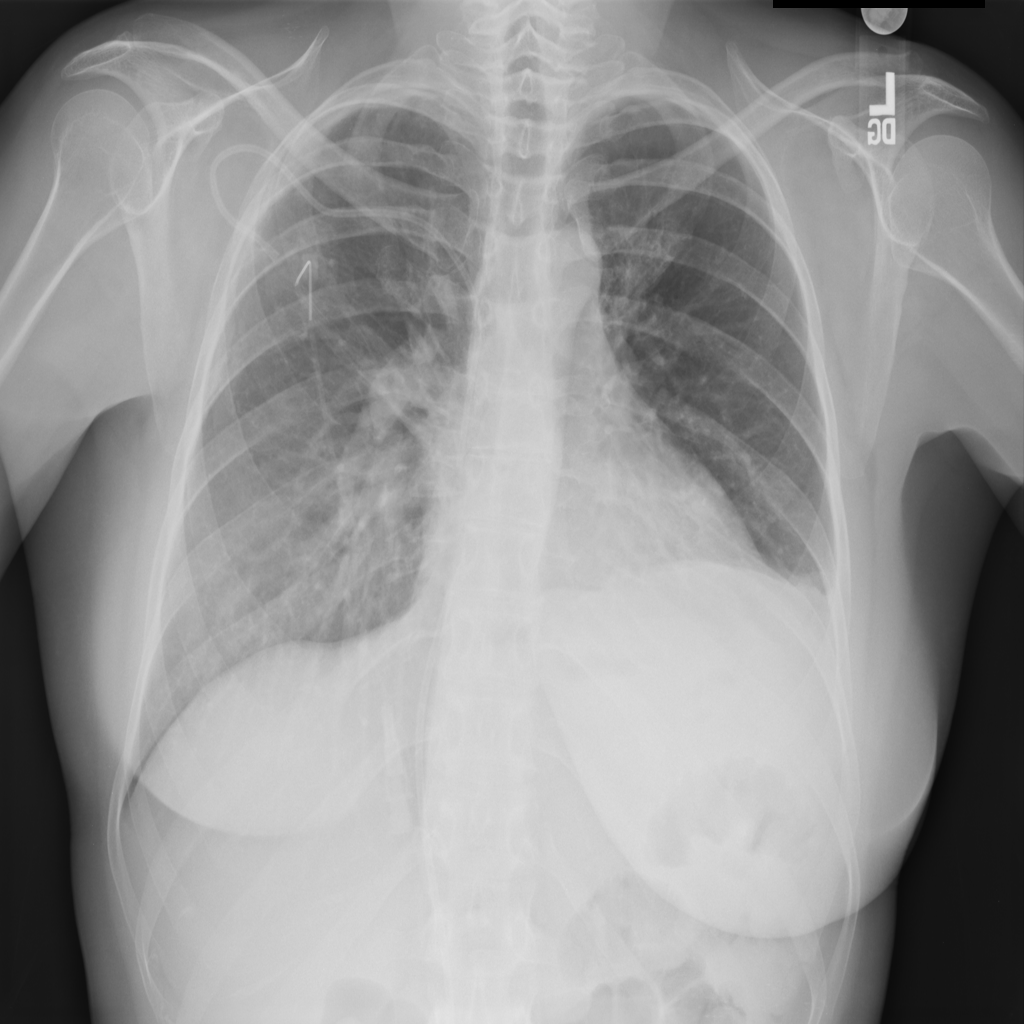

PAT-E960 · IMG-002Fibrosis

PAT-E960 · IMG-002

PA